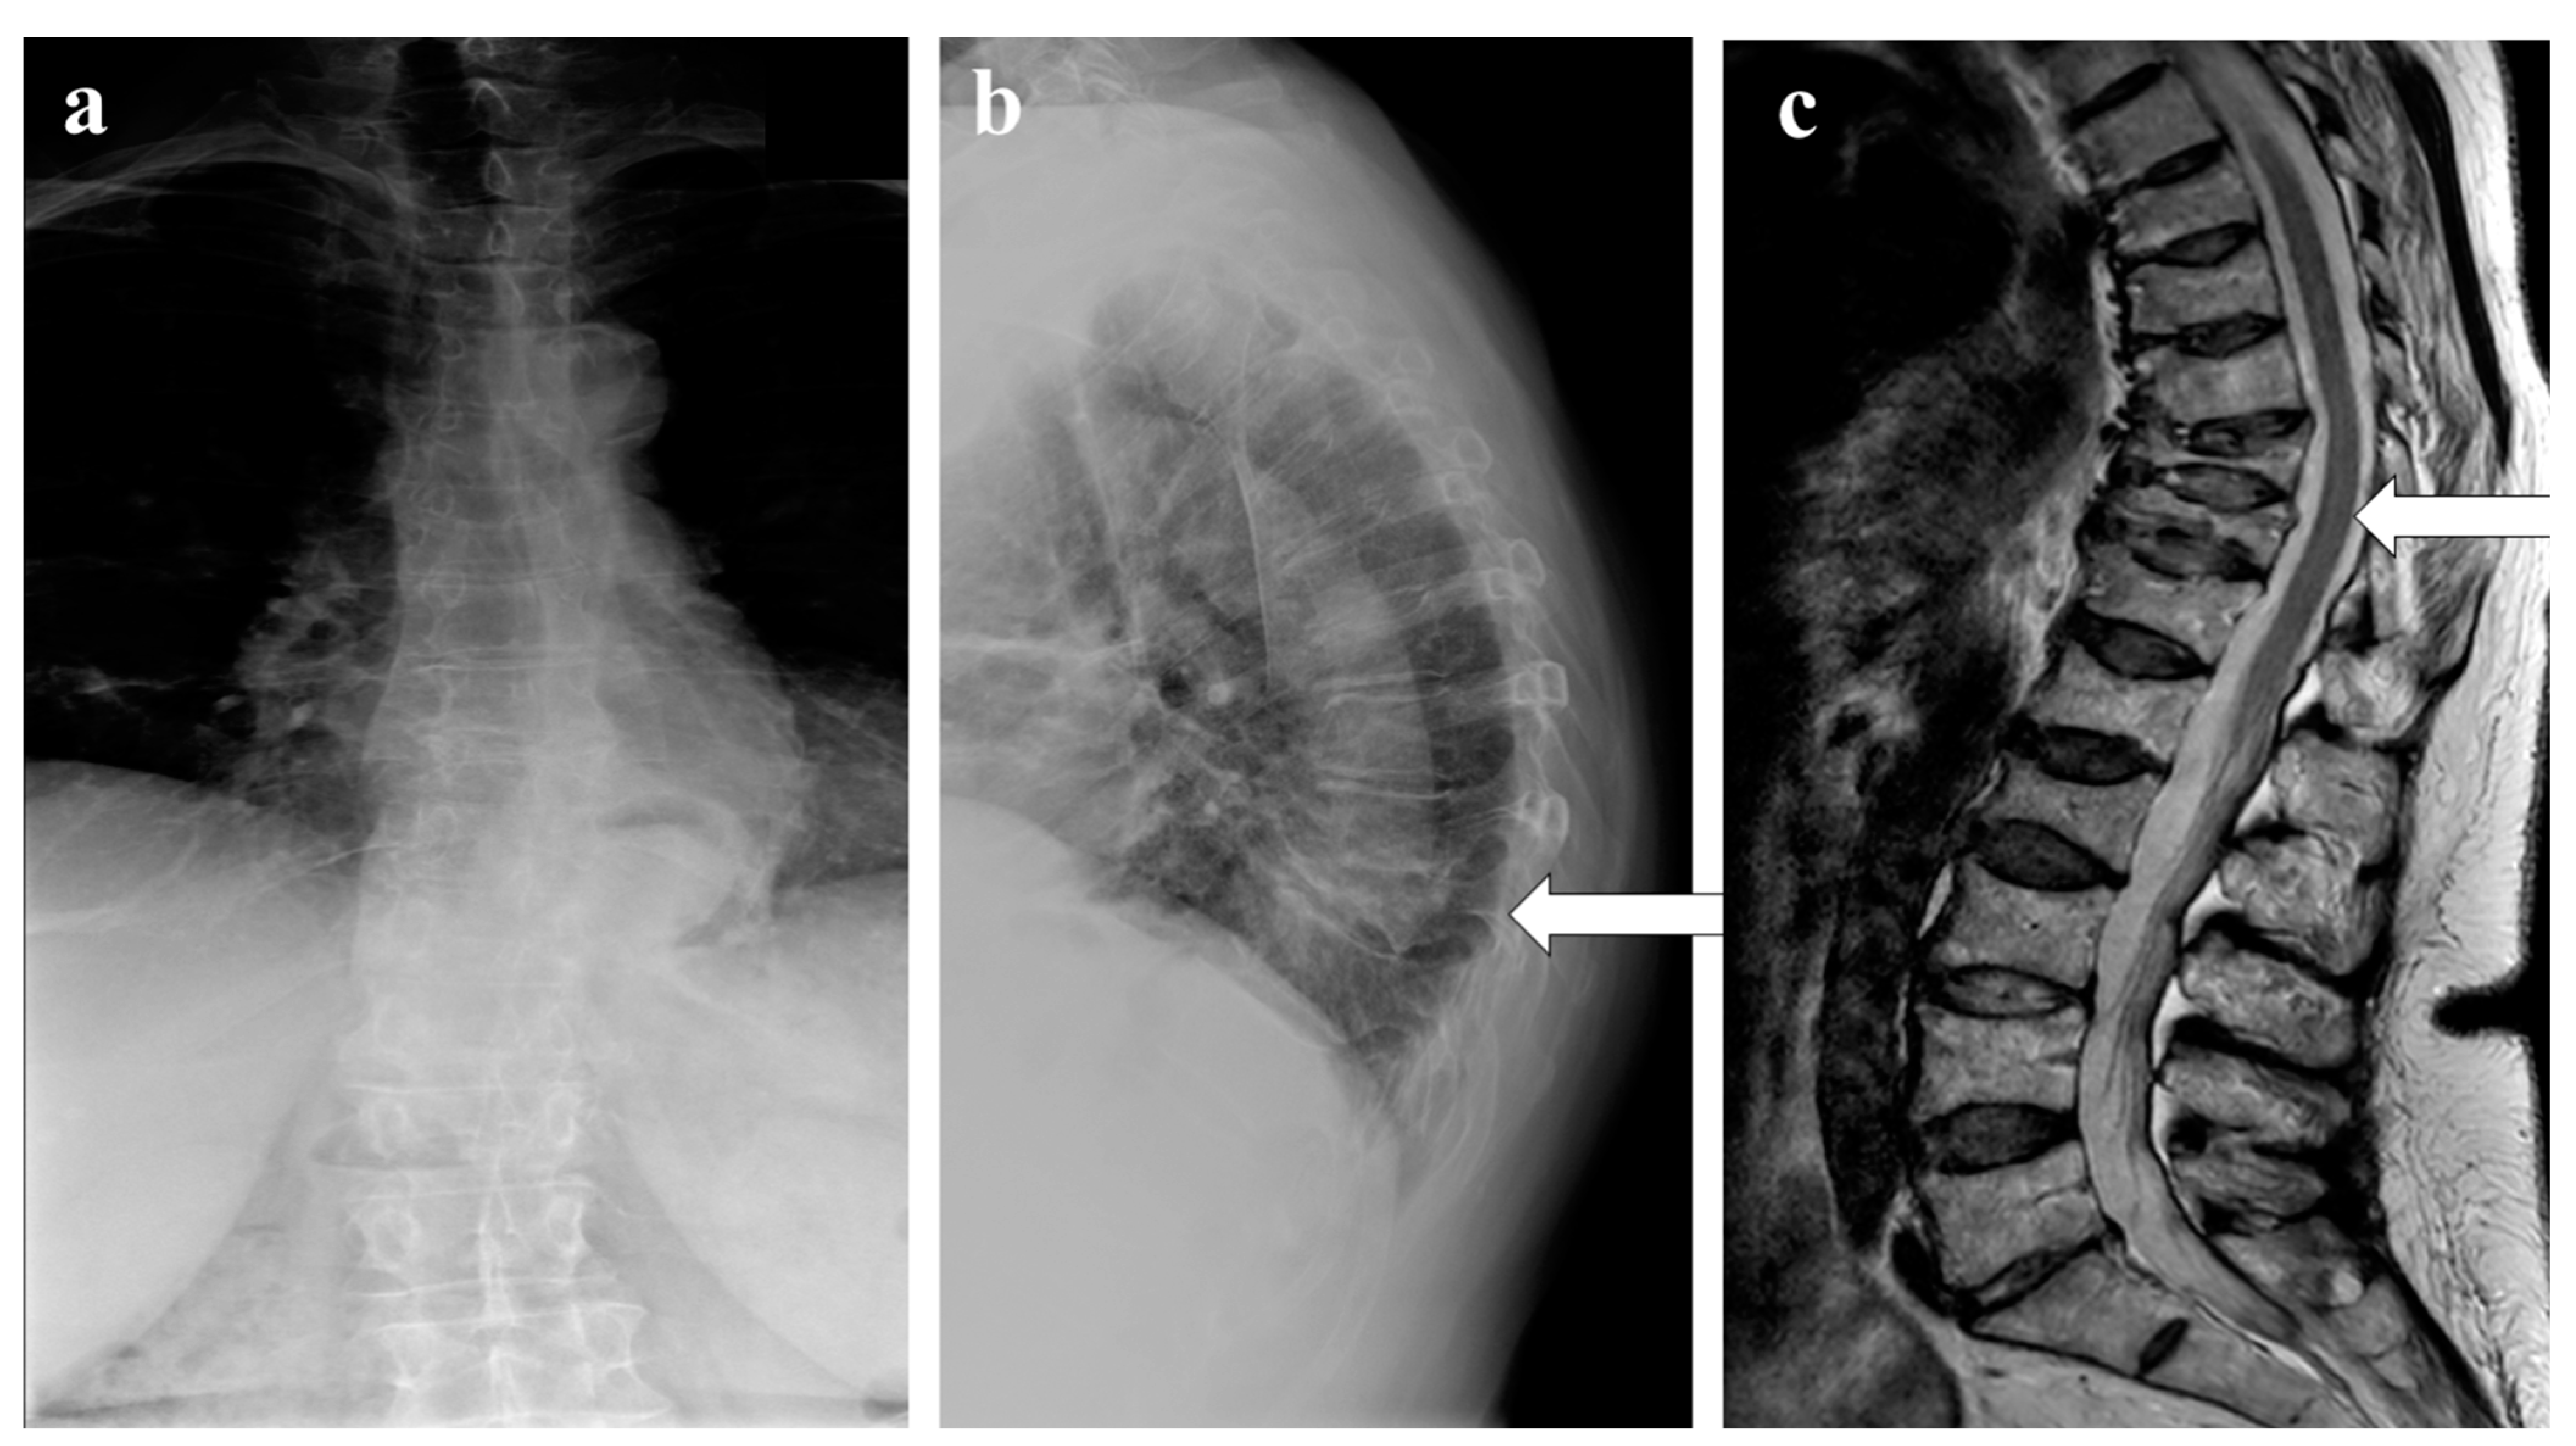

Infections

- Sureka, J.; Samuel, S.; Keshava, S.; Venkatesh, K.; Sundararaj, G. MRI in patients with tuberculous spondylitis presenting as vertebra plana: A retrospective analysis and review of literature. Clin. Radiol. 2013, 68, e36–e42. [Google Scholar] [CrossRef]